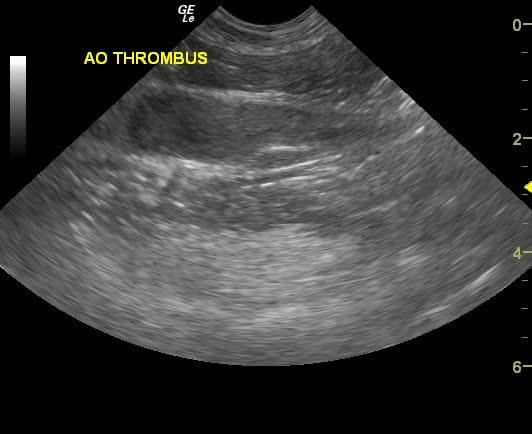

The aorta and left iliac artery were almost completely obstructed by a 6 x 2 cm echogenic thrombus that appeared to be entering into the right iliac artery. The cause of the thrombus could not be ascertained.

Aortic and iliac thrombus. Suspect sepsis or infectious disease. Full coagulation panel, Plavix therapy, Doxycycline and Clindamycin combination would be recommended. Prognosis is extremely guarded. Recheck sonogram in 5-7 days.